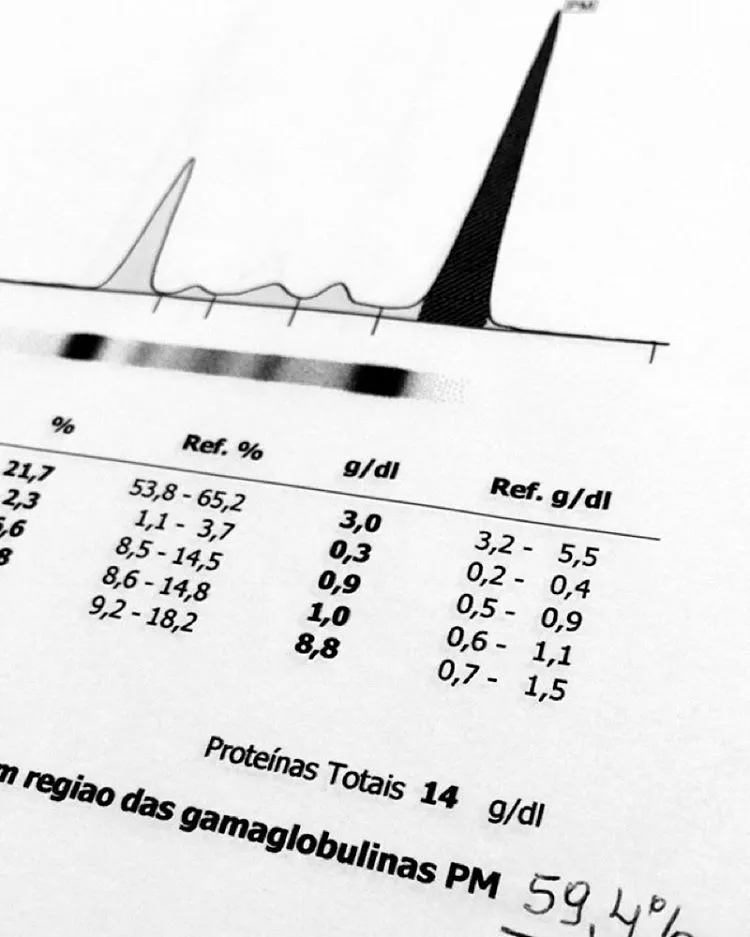

Este vídeo apresenta, de forma didática e baseada em evidências, os principais achados da tese de doutorado sobre amiloidose renal, com foco em proteômica glomerular e ativação do complemento. São discutidos aspectos diagnósticos, implicações fisiopatológicas e correlações clínico-patológicas relevantes para a prática do nefrologista. O conteúdo sintetiza dados inéditos de matriz extracelular glomerular e diferencia perfis entre subtipos de amiloidose. Trata-se de um material aprofundado e acessível, ideal para atualização de especialistas na área.